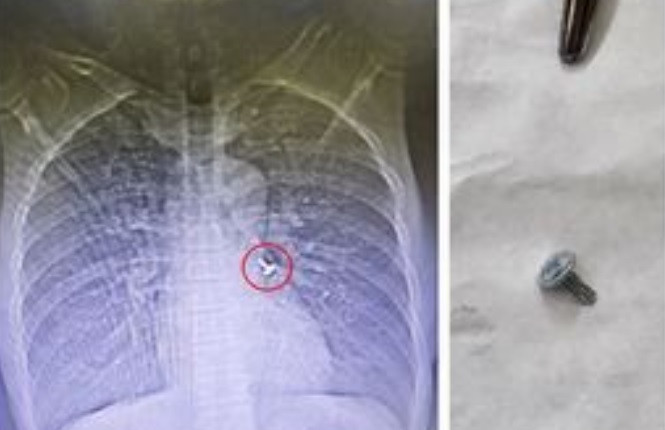

Kết quả chụp cắt lớp lồng ngực cho thấy hình ảnh dị vật sắc nhọn ở vị trí phế quản đáy trái. Bệnh nhân được chỉ định nội soi phế quản cấp cứu lấy dị vật.

Kíp bác sĩ khoa Hô hấp và Bệnh nghề nghiệp đã tiến hành nội soi phế quản dưới gây mê và gắp thành công dị vật là 1 chiếc đinh vít dài khoảng 1 cm có đầu sắc nhọn.

| Hình ảnh đinh vít trong phế quản bệnh nhân và được lấy ra - Ảnh BVCC |

Đinh vít nhọn trong phế quản bệnh nhân được kíp bác sĩ khoa Hô hấp & Bệnh nghề nghiệp gắp ra thành công